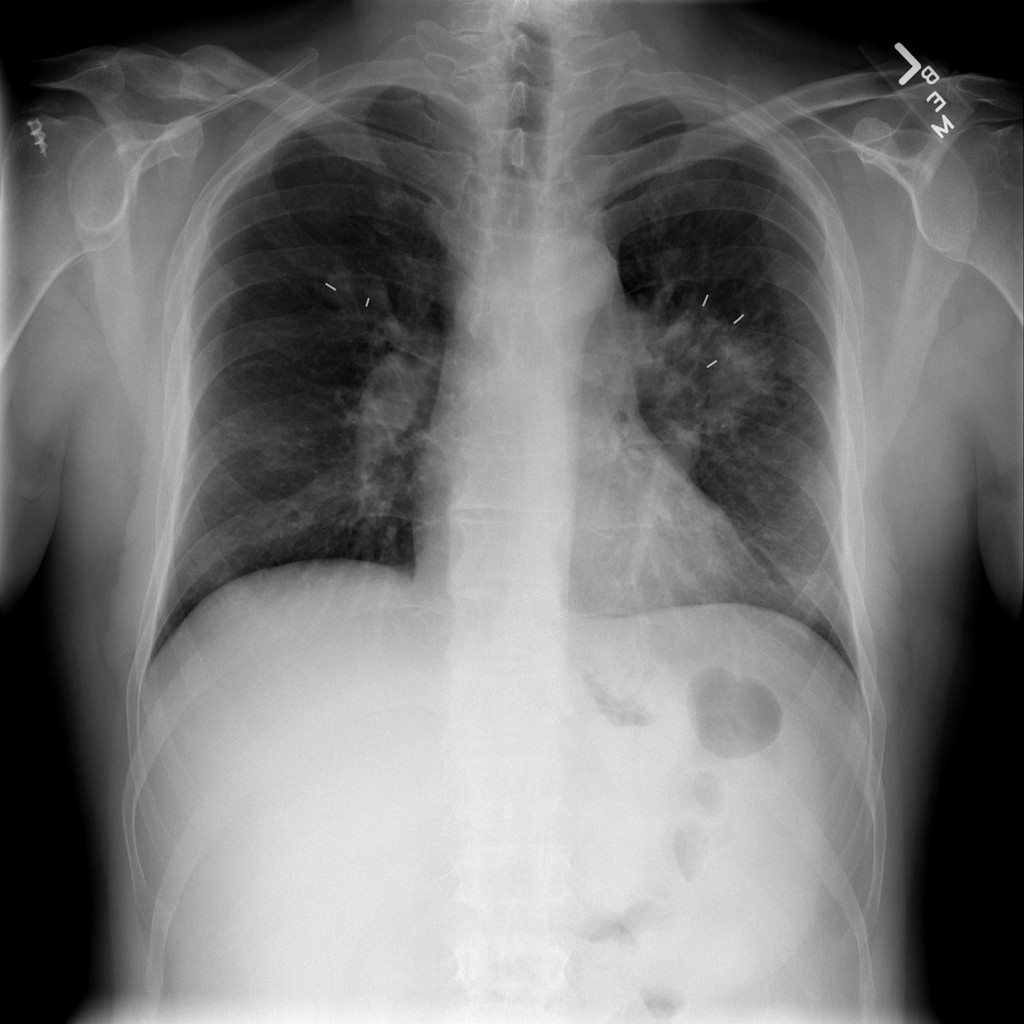

PAT-C0E5 · IMG-001Mass

PAT-C0E5 · IMG-001

PA